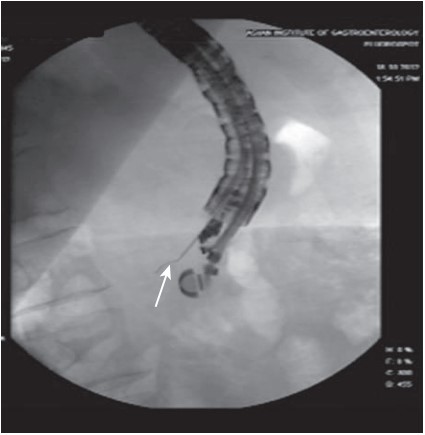

Innovative techniques such as radiofrequency ablation and brachytherapy are being explored to extend the capabilities of EUS-guided treatments further. These methods are especially considered for patients unfit for surgery or those needing palliative control of locally advanced cancers. While these advanced techniques show promising preliminary data, they remain under clinical investigation, highlighting the dynamic nature of gastroenterological research.

Although many EUS-based techniques primarily target the ablation or control of pancreatic malignancies, they also play a vital role in enhancing the delivery of radiation therapy. This is achieved through the placement of radiopaque markers directly into the tumor, facilitating targeted treatment and potentially improving outcomes for patients with various types of cancers.